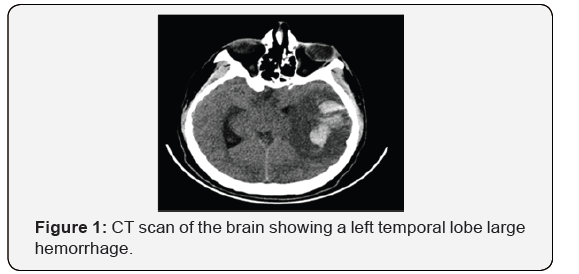

An 18-year-old right-handed male presented to the Emergency Department (ED) with right-sided weakness. He is known to have sickle cell anemia on folic acid. He was a smoker. He had no history of previous neurological manifestations or systemic vaso-occlusive crisis. His physical examination revealed aphasia and right-sided hemiplegia. During ED visit, his consciousness level deteriorated and he required intubation. His CT scan of the brain revealed a left temporal lobe large hemorrhage with significant vasogenic edema and midline shift (Figure 1). He required immediate decompressive hemicraniectomy. Intraoperatively, a thrombosis of the left vein of Labbe was noted. Although Magnetic Resonance Venography (MRV) showed patent main venous sinuses, a four-vessel cerebral angiography demonstrated the paucity of the left convexity cortical veins, confirming a cortical and/or deep venous thrombosis (Figure 2).